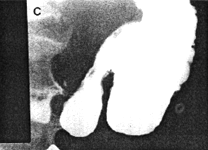

Case 29.1 C.W., 60 year old male, presented with intermittent epigastric pain and malaena. Radiographic examination showed a gastric ulcer, 2.5 cm in diameter, in the posterior wall of the upper corpus, approximately 10 cm proximal to the pylorus; the features were those of a benign ulcer. There was constant contraction (or spasticity) of the pyloric sphincteric cylinder, the contracted region being 3.0 to 4.0 cm in length (Fig. 29.1). Cyclical contraction and relaxation of the cylinder, normally occurring at a rate of 3 cylces per minute, was absent; the contraction of the cylinder "fixed" the pyloric aperture in the open or patent position. Mucosal folds in the contracted cylinder appeared normal, but their movements were restricted. A shallow, concave identation of the base of the duodenal bulb, caused by the pyloric ring, was evident. Peristaltic waves in the remainder of the stomach were normal; emptying of liquid barium appeared normal. Two weeks later a Billroth I partial gastrectomy confirmed the large, chronic gastric ulcer. No macroscopic abnormality was seen or felt in the pyloric region. Histology of the ulcer proved it to be benign; microscopic examination of the pyloric region was not carried out.

| Fig. 29.1 A-D. Case C.W. Constant contraction or spasticity of pyloric sphincteric cylinder. Cyclical activity absent. Pyloric aperture "fixed" in patent position (B-D) | |